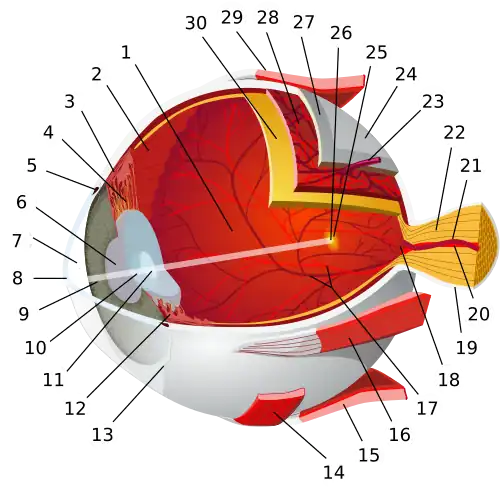

| |

1. vitreous body 2. ora serrata 3. ciliary muscle 4. ciliary zonules 5. Schlemm's canal 6. pupil 7. anterior chamber 8. cornea 9. iris 10. lens cortex 11. lens nucleus 12. ciliary process 13. conjunctiva 14. inferior oblique muscle 15. inferior rectus muscle 16. medial rectus muscle 17. retinal arteries and veins 18. optic disc 19. dura mater 20. central retinal artery 21. central retinal vein 22. optic nerve 23. vorticose vein 24. bulbar sheath 25. macula 26. fovea 27. sclera 28. choroid 29. superior rectus muscle 30. retina | |

The eye can be considered as a living optical device. It is approximately spherical in shape, with its outer layers, such as the outermost, white part of the eye (the sclera) and one of its inner layers (the pigmented choroid) keeping the eye essentially light tight except on the eye's optic axis. In order, along the optic axis, the optical components consist of a first lens (the cornea—the clear part of the eye) that accounts for most of the optical power of the eye and accomplishes most of the focusing of light from the outside world; then an aperture (the pupil) in a diaphragm (the iris—the coloured part of the eye) that controls the amount of light entering the interior of the eye; then another lens (the crystalline lens) that accomplishes the remaining focusing of light into images; and finally a light-sensitive part of the eye (the retina), where the images fall and are processed. The retina makes a connection to the brain via the optic nerve. The remaining components of the eye keep it in its required shape, nourish and maintain it, and protect it.

The eye is not shaped like a perfect sphere; rather it is a fused two-piece unit, composed of an anterior (front) segment and the posterior (back) segment. The anterior segment is made up of the cornea, iris and lens. The cornea is transparent and more curved and is linked to the larger posterior segment, composed of the vitreous, retina, choroid and the outer white shell called the sclera. The cornea is typically about 11.5 mm (0.45 in) in diameter, and 0.5 mm (500 μm) in thickness near its centre. The posterior chamber constitutes the remaining five-sixths; its diameter is typically about 24 mm (0.94 in). An area termed the limbus connects the cornea and sclera. The iris is the pigmented circular structure concentrically surrounding the centre of the eye, the pupil, which appears to be black. The size of the pupil, which controls the amount of light entering the eye, is adjusted by the iris' dilator and sphincter muscles.

Light energy enters the eye through the cornea, through the pupil and then through the lens. The lens shape is changed for near focus (accommodation) and is controlled by the ciliary muscle. Between the two lenses (the cornea and the crystalline lens), there are four optical surfaces which each refract light as it travels along the optical path. One basic model describing the geometry of the optical system is the Arizona Eye Model.[2] This model describes the accommodation of the eye geometrically. Photons of light falling on the light-sensitive cells of the retina (photoreceptor cones and rods) are converted into electrical signals that are transmitted to the brain by the optic nerve and interpreted as sight and vision.

The eye is made up of three coats, or layers, enclosing various anatomical structures. The outermost layer, known as the fibrous tunic, is composed of the cornea and sclera, which provide shape to the eye and support the deeper structures. The middle layer, known as the vascular tunic or uvea, consists of the choroid, ciliary body, pigmented epithelium and iris. The innermost is the retina, which gets its oxygenation from the blood vessels of the choroid (posteriorly) as well as the retinal vessels (anteriorly).

The spaces of the eye are filled with the aqueous humour anteriorly, between the cornea and lens, and the vitreous body, a jelly-like substance, behind the lens, filling the entire posterior cavity. The aqueous humour is a clear watery fluid that is contained in two areas: the anterior chamber between the cornea and the iris, and the posterior chamber between the iris and the lens. The lens is suspended to the ciliary body by the suspensory ligament (zonule of Zinn), made up of hundreds of fine transparent fibers which transmit muscular forces to change the shape of the lens for accommodation (focusing). The vitreous body is a clear substance composed of water and proteins, which give it a jelly-like and sticky composition.[6]